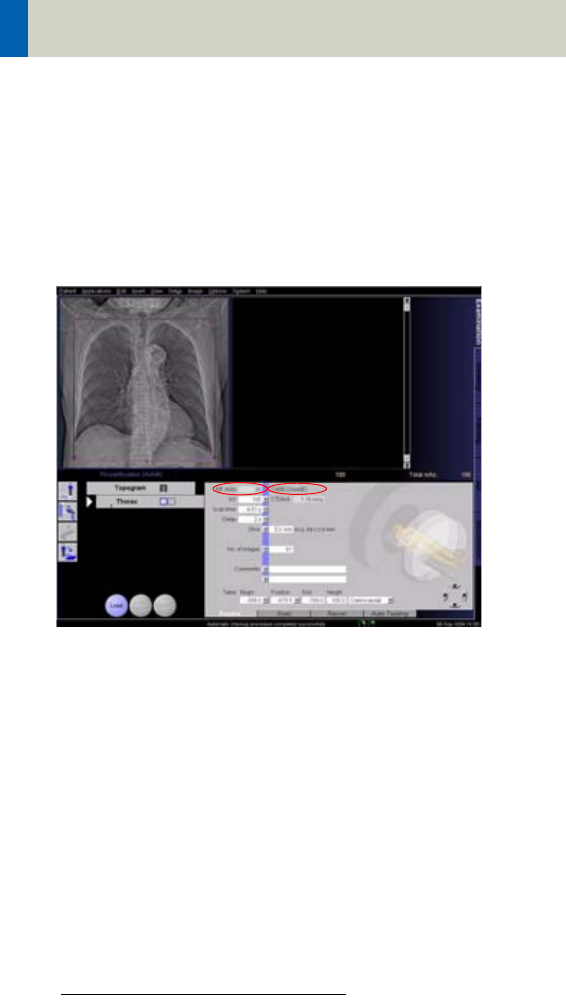

The Quality reference mAs value is displayed on the

Scan tab card. This defines the overall image quality of

the scan protocol currently being used. This value can

be adapted for each protocol according to the user’s

individual requirements of image quality. Here you can

also view the effective mAs value that the system is

going to use for the current scan range.

You can also deselect CARE Dose4D on this tab card.